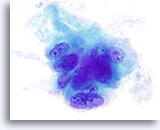

Zeer waarschijnlijk benigne

In deze categorie vallen die folliculaire laesies die een macrofolliculair of gemengd micro- en macrofolliculair patroon vertonen met weinig tot overvloedig colloïde op de achtergrond. Op ThinPrep zijn macrofollikels te zien als lagen van tientallen gelijkmatig verdeelde folliculaire cellen met een goede afstand tussen kernen. De significantie van losse folliculaire cellen op ThinPrep in onzeker, omdat deze worden waargenomen in een verder micro- of macrofolliculair patroon. Omdat de waarschijnlijkheid dat deze laesies maligniteit vertonen (folliculaire variant van papillair carcinoom of folliculair carcinoom) bij histologie laag is, maar niet helemaal nul (in de literatuur varieert het percentage van 0 tot 43%) [6, 9, 12, 13, 14, 15, 16, 17, 18, 19, 20, 21, 24, 25, 26, 27] waarbij op drie na[14, 16, 27] alle studies minder dan 6% rapporteerden, noemen we dit daarom zeer waarschijnlijk benigne in plaats van onmiskenbaar benigne.